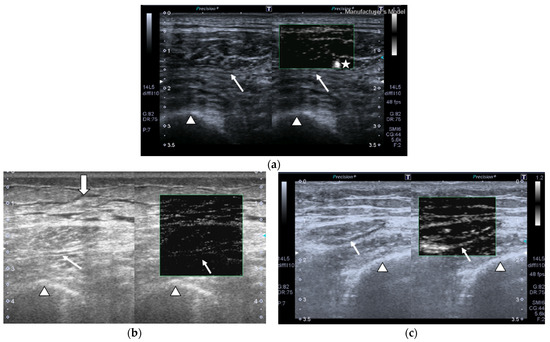

SMI images of a patient and a healthy control are displayed in Figure 2.

Transversal QRF muscle US scan and the superb microvascular imaging (SMI) built-in software that indicates microvascularization. (a)Transversal QRF muscle (arrow) US scan, femur (arrowhead). SMI image shows dot-like vessels and a penetrating vessel (star) for a matched healthy control (60 years old). (b) Transversal QRF muscle (arrow) US scan, femur (arrowhead); subcutaneous edema with intramuscular and interfacial fluid (thick arrow). SMI image shows dot-like vessels for a patient with multiorgan failure (58 years old). (c) Transversal QRF muscle (arrow) US scan, femur (arrowhead). SMI image shows minimal linear vessels for another patient with multiorgan failure (51 years old).